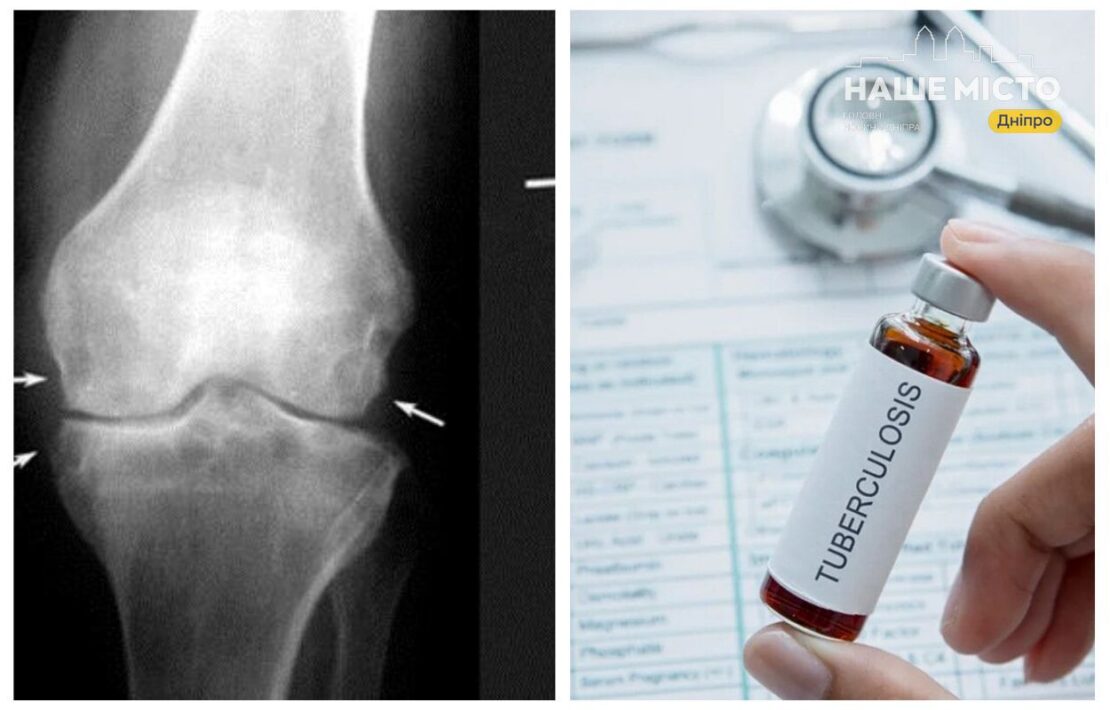

У Дніпропетровському медичному центрі проводять комплексні обстеження, які включають аналізи сечі, мазки та дослідження на присутність туберкульозної палички (GeneXpert). Ураження кісток і центральної нервової системи потребують тривалішого лікування, що може тривати від 9 до 10 місяців.